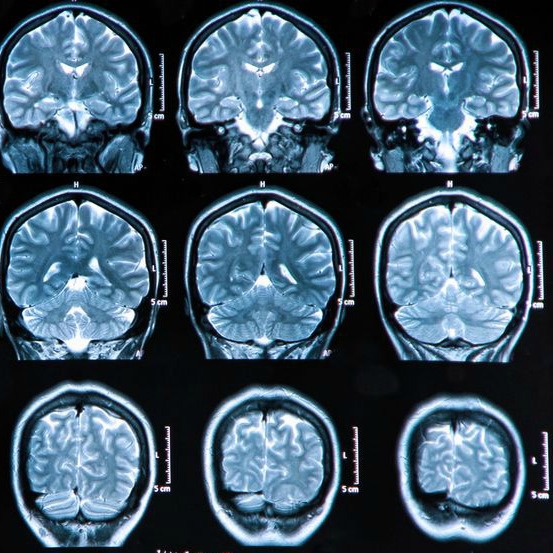

Scleroza multipla cunoscuta si sub denumirea de scleroza in placi este o afectiune inflamatorie a creierului si a maduvei spinarii a sistemului nervos central. Este o boala inflamatorie cronica autoimuna a sistemului nervos central caracterizata prin demielinizare neuronala localizata multifocala evoluand cu formarea de placi de scleroza. Scleroza multipla scleroza in placi leuconevraxita scleroza multipla sm este o boala inflamatorie si degenerativa a sistemului nervos central snc care afecteaza creierul maduva spinarii si nervii optici. Forma recurent remisiva si forma primar progresiva.

Scleroza multiplă este o boală care debutează la adultul tânăr 20 40 ani şi este de 2 3 ori mai frecventă la femei decât la bărbaţi. Scleroza in placi sau scleroza multipla este o boala in care nervii sistemului nervos central adica ai creierului si maduvei spinarii nu mai functioneaza cum trebuie imbolnavindu se treptat. Leziunile care apar in substanta nervoasa in teaca de mielina a axonilor se caracterizeaza prin focare multiple de demielinizare si cicatrizare scleroza de unde si denumirea de scleroza multipla. Scleroza in placi atinge in principal adultii tineri de ambele sexe cu predominanta feminina 60 dintre cazuri.